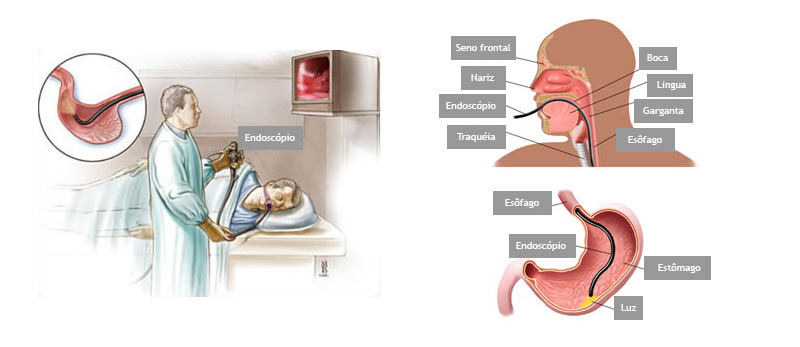

É um exame indicado para avaliação diagnóstica e tratamento das doenças da parte superior do tubo digestivo, incluindo o esôfago, o estômago e a porção inicial do duodeno.

Realizado introduzindo-se pela boca um aparelho flexível com iluminação central que permite a visualização de todo o trajeto examinado.

O exame é realizado com anestesia tópica (um spray de anestésico na garganta) e com sedação, utilizando medicação administrada por uma veia para permitir que você relaxe e adormeça.

O que acontecerá durante o exame ?

Você não sentirá dor, as vezes apenas um leve desconforto na garganta durante a passagem do aparelho e no estômago durante a insuflação do órgão com ar.

É um exame indicado para avaliação diagnóstica e tratamento das doenças da parte superior do tubo digestivo, incluindo o esôfago, o estômago e a porção inicial do duodeno.

Realizado introduzindo-se pela boca um aparelho flexível com iluminação central que permite a visualização de todo o trajeto examinado.

O exame é realizado com anestesia tópica (um spray de anestésico na garganta) e com sedação, utilizando medicação administrada por uma veia para permitir que você relaxe e adormeça.

O que acontecerá durante o exame ?

Você não sentirá dor, as vezes apenas um leve desconforto na garganta durante a passagem do aparelho e no estômago durante a insuflação do órgão com ar.